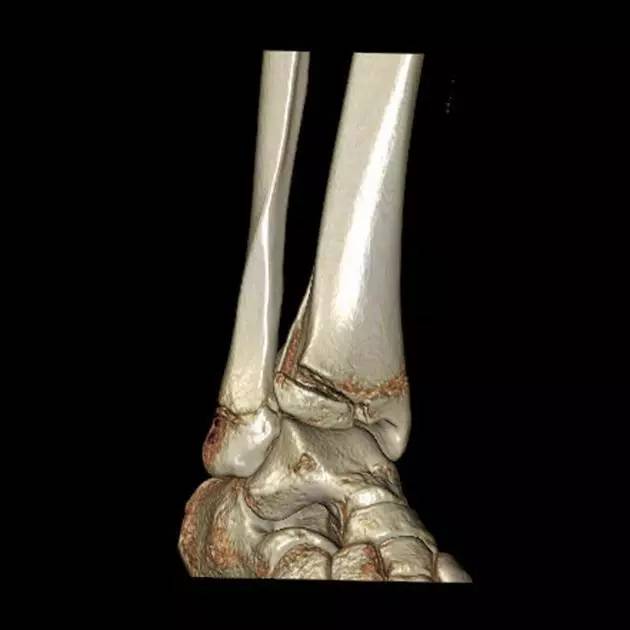

1. 三平面骨折(Triplane fracture )

即累及远端胫骨骨骺的骨折可因骨折线延入其他两个平面而变得复杂,因而称之。骨折由矢状面内的骨骺骨折,经生长板外侧面的轴位面内水平方向骨折,与冠状面内经干骺端到骨干的斜行骨折,自生长板的前侧面伸延至胫骨的后侧皮质。

图为一 12 岁女孩左踝典型的三平面骨折

三平面骨折 CT 片

三平面骨折 CT 重建